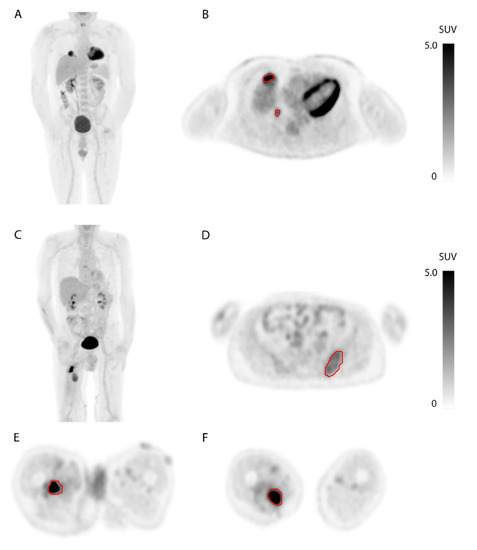

2.3. [18F]FDG-PET/CT

2.4. [18F]]FDG-PET Features